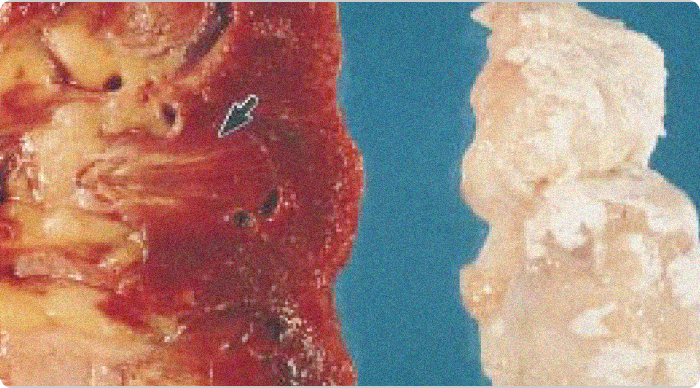

Images of gouty tophi in joint and kidney

Gouty tophi in joint and kidney. Chalky white urate deposits are visible in the articular cartilage (right). The corresponding kidney (left) shows yellowish areas in the pyramids (arrow) representing fibrosis and urate deposits.1

Adapted from Nickeleit V, et al. Nephrol Dial Transplant. 1997;12:1832-1838.

KRYSTEXXA has not been studied to reverse damage to the kidneys or any of the body's organs.